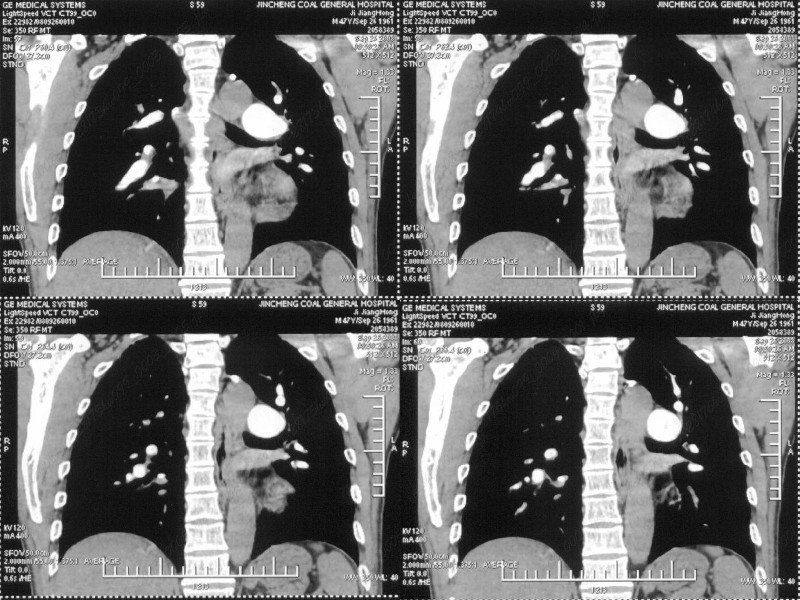

男性,47岁。胸部不适一年,ct检查发现右胸膜下结节。http://www.radida.com/bbs/forum.php?mod=viewthread&tid=46094

图像很清,资料很全。工作做的很细,向您学习!观阁下的强化图像发现,您们强化后扫描时间挺早,延迟时间大约在16—18秒之间吧。估计目的是为了观察肺动脉及分支的情况。但现有的资料并不能提示动脉栓塞改变。建议楼主可在机器上仔细观察,或许会有异常发现。另外,个人感觉右侧应为肺内结节而非胸膜结节。考虑肺内良性小结节,炎性假瘤可能性大。

病灶周围似有纤维化征像,增强明显强化,但中央可见点状低强化区,考虑慢性病变可能如炎性假瘤等,病灶边缘部分毛糙有切迹,双侧胸腔少量积液影,不除外恶性

右肺中叶外侧段胸膜下结节状病灶,性质待定(不排除周围型肺癌可能)。

小结节的周围似乎与斜裂的走行有关,边缘分界不很清楚,与侧胸膜关系密切,有轻度强化,不能除外恶性,建议密切观察。

汇报临床诊断:右肺动脉分枝栓塞

右肺静脉充盈缺损,左心房体积小,右肺动脉远端动脉充盈缺损,右肺血管影细小,考虑;右肺动脉远端栓塞.